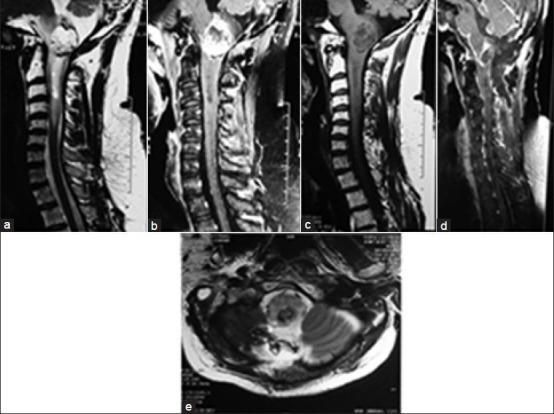

Patients admitted in the Department of Neurosurgery with a diagnosis of CMJ intramedullary tumors from January 2001 to January 2010 were included in the study. Patients were analyzed retrospectively regarding their symptomatology, clinical findings, radiology and outcome after surgery. All patients underwent pre-operative magnetic resonance imaging (MRI) and post-operatively all were managed in the neurosurgery intensive care unit for days to weeks or as dictated by the clinical condition of the patient.

A total of 32 patients were included in the present study. The number of males was 21 (65.6%) and females were 11 (34.4%) respectively. The mean age of presentation was 22.97 ± 9.8 years and the mean duration of pre-operative symptoms was 13.3 ± 12.9 months. The tumor had extension from the CMJ into the cervical region in 17 (53.1%) and into the medullary region in 14 (43.8%) patients. Tumor decompression was done in 9 (28.1%) patients and gross near total excision done in 23 (71.87%) patients.

Cervicomedullary tumors are a subset of tumors quite distinct from the usual brainstem tumors. Patients having predominant cervical involvement present early and have less post-operative deficits. Those with predominantly more medullary involvement present late, hence have a much more morbid outcome. Though closely related to vital neural structures, surgery forms the mainstay of treatment. Adequate pre-operative planning and preparation of the patient along with intense post-operative monitoring and ventilatory assistance as and when required helps in a good surgical outcome.

纳入2001年1月至2010年1月在神经外科确诊为CMJ髓内肿瘤的患者。对患者的症状、临床表现、影像学检查及术后结果进行回顾性分析。所有患者术前行磁共振成像(MRI)检查,术后均在神经外科重症监护病房治疗数天至数周,或根据患者的临床情况而定。

本研究共纳入32例患者。男性21例(65.6%),女性11例(34.4%)。平均就诊年龄为22.97±9.8岁,术前症状平均持续时间为13.3±12.9个月。17例(53.1%)患者的肿瘤从CMJ延伸至颈部区域,14例(43.8%)患者的肿瘤延伸至延髓区域。9例(28.1%)患者进行了肿瘤减压,23例(71.87%)患者进行了大体近全切除。

颈髓肿瘤是一类与常见脑干肿瘤截然不同的肿瘤。以颈部受累为主的患者就诊早,术后缺损较少。以延髓受累为主的患者就诊晚,因此预后更差。尽管与重要神经结构密切相关,但手术仍是主要的治疗方法。充分的术前规划和患者准备,以及必要时的术后密切监测和通气支持有助于取得良好的手术效果。